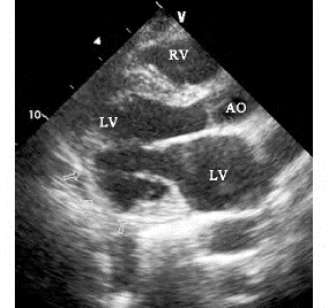

图19-11 室壁变薄二维超声图

左室后下壁室壁变薄,局部略向外膨出,心肌回声增强